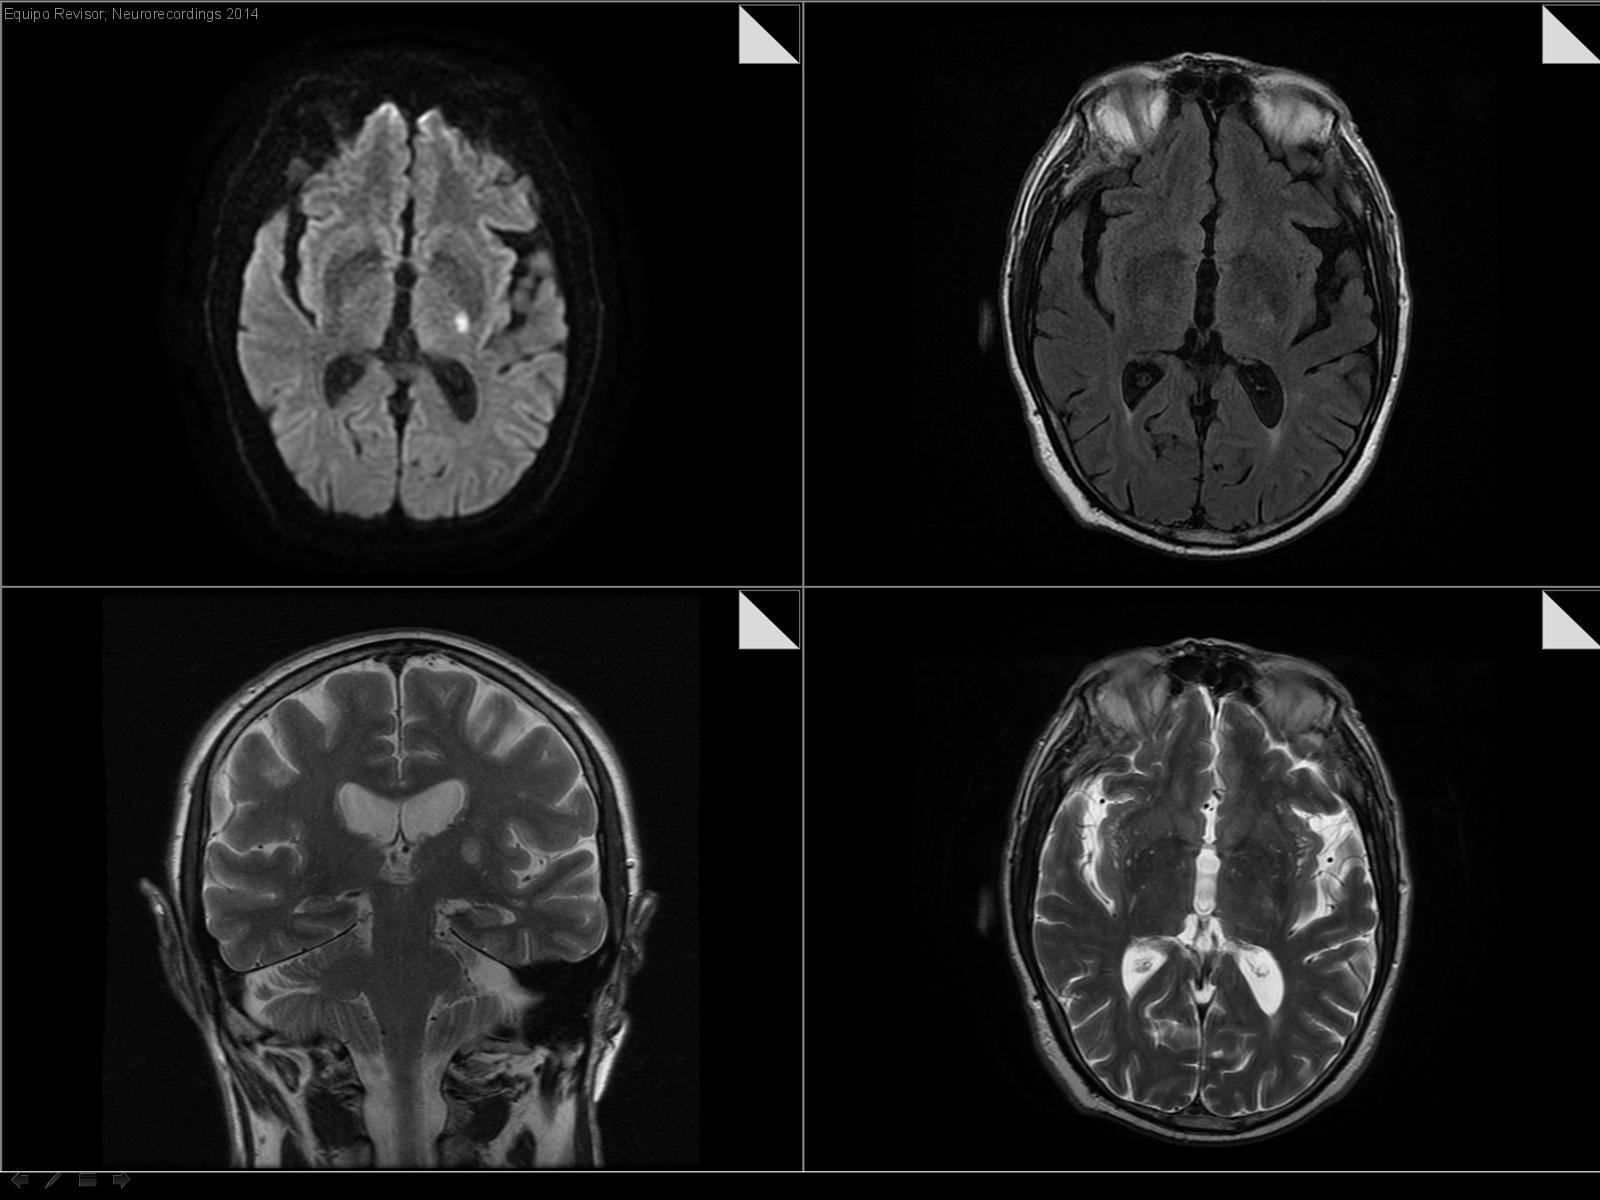

Hemiparesia derecha sin alteracion del lenguaje

Hombre | 68 años

Diagnóstico final: Ictus lacunar motor puro derecho

Neurología: Patología cerebrovascular

Etiología: Ictus